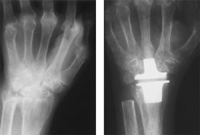

X-ray of a wrist with severe rheumatoid arthritis throughout the wrist before (left) and after (right) replacement of the wrist joint with a silicone rubber implant.

Reproduced with permission from Carlson JR, Simmons BP: Total Wrist Arthroplasty. J Am Acad Orthop Surg 1998;6:308-315.